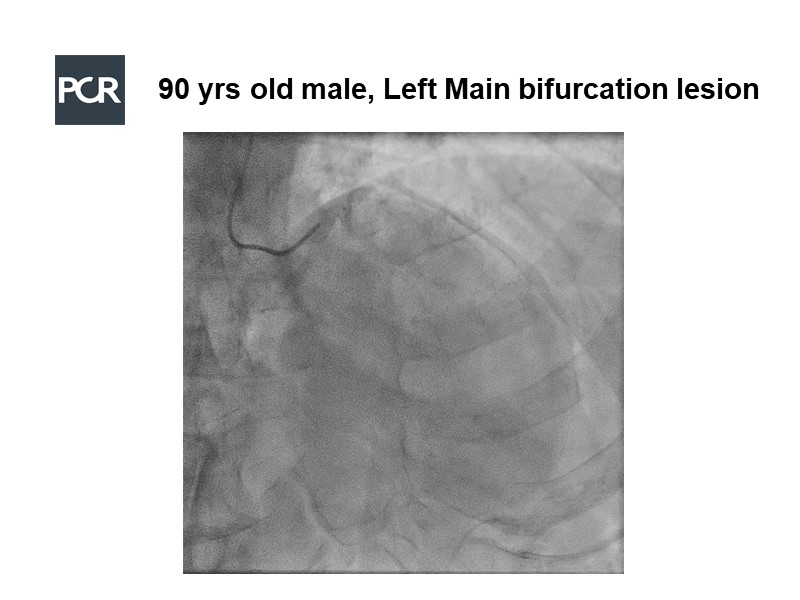

View the life challenging case of a 90-year-old male patient with a very active lifestyle but hypertension, dyslipidemia, ex-smoker, who presented with left main bifurcation lesion, and appreciate the value of transradial approach for left main and complex bifurcation PCI, acknowledge Ultimaster DES results in bifurcations and high bleeding risk patients, and understand how to optimise strategy and technique using intra-coronary imaging.